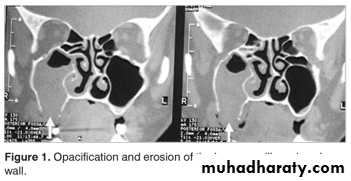

Choanal Atresia

Congenital atresia of the posterior nares due to persistence of the bucconasal membrane, usually unilateral but bilateral cases can occur and observed at birth because the neonate is obligate nasal breather.The obstruction either composed of bone (most commonly) or membrane.

The condition occurs in 1 out of every 7,000 to 8,000 live births.

Clinical Picture

Females are commonly affected than males.Bilateral Neonatal emergency leads to asphyxia because the infant is obligate nasal breather and commonly associated with other congenital anomalies.

Unilateral-(60%) with a right-sided predominance nasal obstruction and excessive nasal discharge in the affected side which may be not noticed for some years.

Examination

1. Total absence of nasal air flow by mirror test and cotton test.

2. Plastic catheter or probe can’t be passed through the affected side to the nasopharynx.

3. Fibroptic endoscopy.

Investigations

Contrast radiography by instillation of radioopaque substance in the affected side.CT scan to see the thickness of a bony atresia.

Treatment

Unilateral elective perforation of the occlusion usually prior starting of school.Bilateral oral airway surgical intervention.